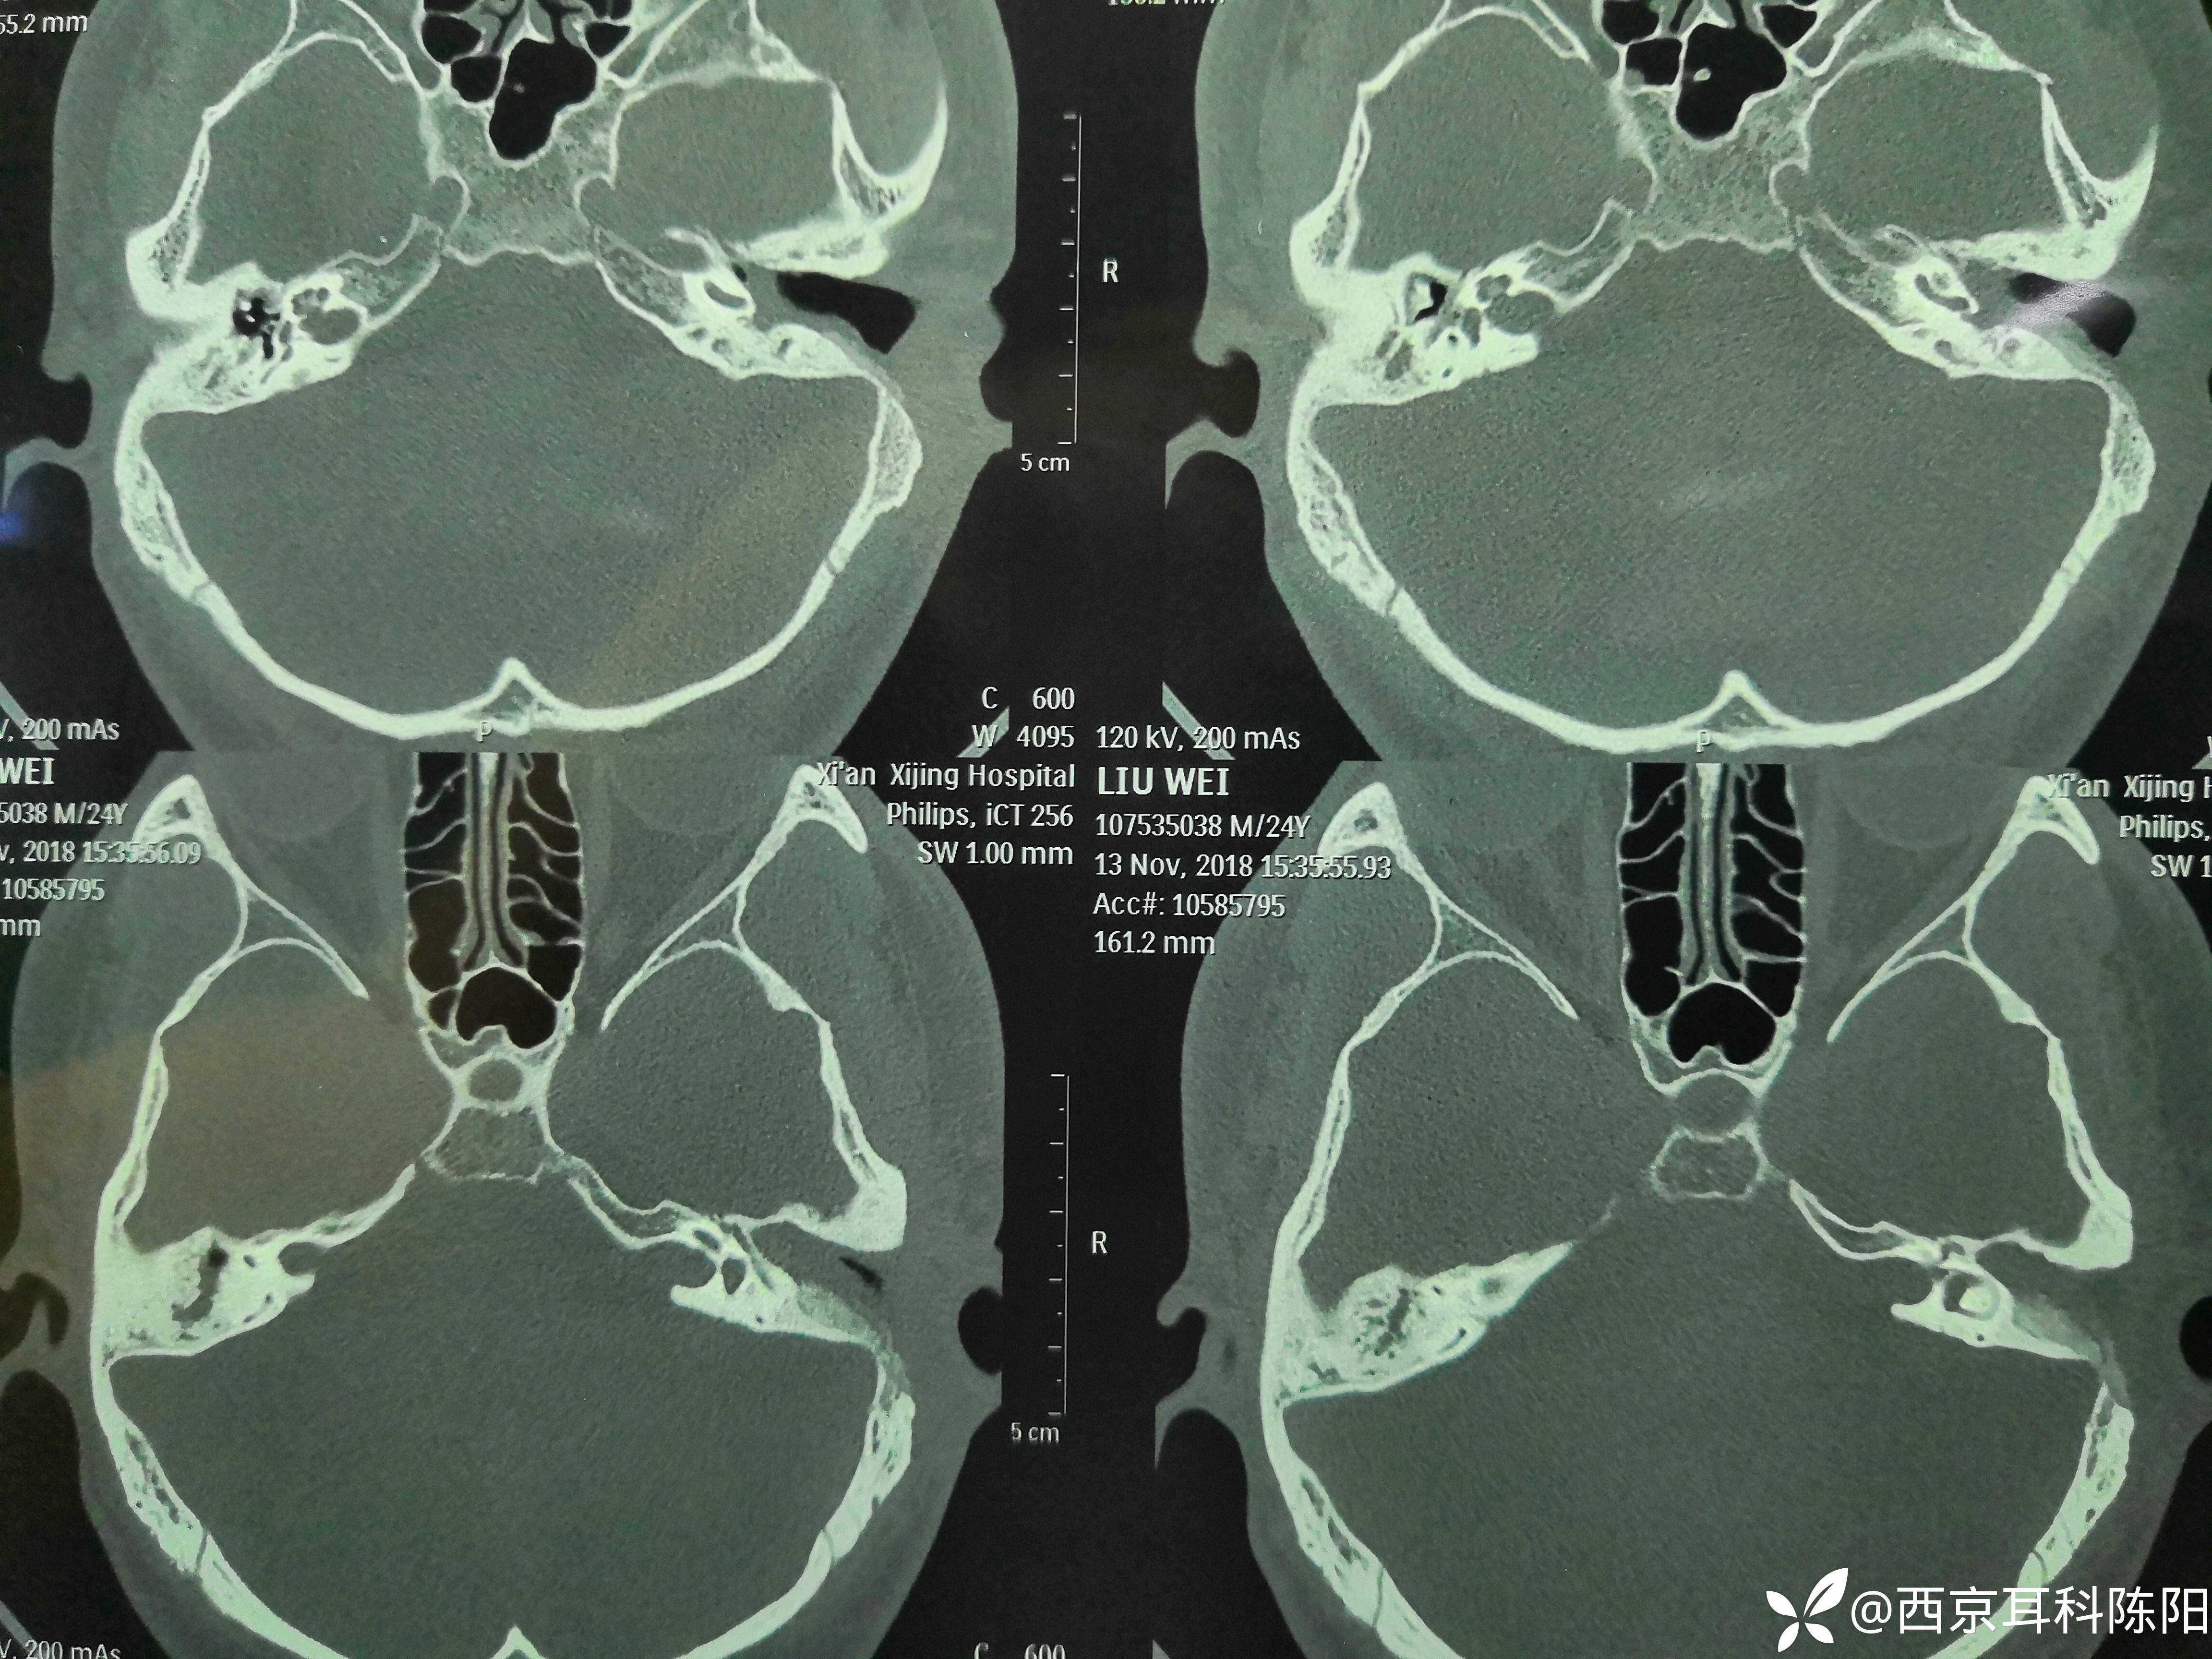

病例2018-11-19的4型鼓室硬化-1期鼓室成形术

钩针清理镫骨和面神经水平段之间的硬化灶后,用自体砧骨塑形桥接镫骨头与锤骨柄